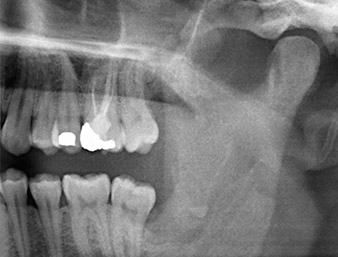

Un patient de 26 ans se plaignait de douleurs permanentes et d’une paresthésie à la suite de l’extraction chirurgicale d’une dent de sagesse incluse. Les radios panoramiques ont confirmé la présence d’un reste radiculaire à proximité étroite du nerf alvéolaire inférieur.

Un patient de 26 ans se plaint de douleurs récurrentes dans la zone opératoire six mois après l’ostéotomie de la dent 38 (LL8) et d’une hyposensibilité dans la zone innervée par le nerf alvéolaire inférieur. Il est adressé par son chirurgien-dentiste référent - qui n'a pas pratiqué l’extraction initiale lui-même - au Département de chirurgie orale de la clinique dentaire universitaire de Vienne.

À l’OPG, le reste radiculaire dans la région de la dent 38 (LL8) apparaît déjà très proche du nerf alvéolaire inférieur. La racine s’est fracturée pendant l’ostéotomie mais n'a pas été extraite par le prestataire de soins primaires en raison de douleurs peropératoires. Pour minimiser le traumatisme causé aux tissus, la nouvelle ostéotomie devait être réalisée par piézochirurgie. Le patient ne présente pas d’antécédents médicaux particuliers et est non-fumeur.

Compte tenu de ses antécédents médicaux, notre patient (26 ans, non-fumeur) présentait de très bonnes chances

de réussite. L’OPG ayant révélé que le reste radiculaire était très proche du nerf alvéolaire inférieur, une tomographie volumétrique numérique a été effectuée en plus (6).